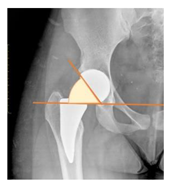

Plain radiographs were evaluated preoperatively and at the most recent follow-up, after appropriate calibration. Positional parameters were assessed according to values guidelines from published literature, as listed in Table 1 [23,24,25,26,27,28,29,30,31]. Femoral stem and acetabular cup osteointegration were quantified according to Engh [32] and Moore scale [33]. Heterotopic ossifications were graded according to the Brooker system [34].

3.4. Radiographic Evaluation

Preoperative and postoperative radiographic data are reported in Table 4. Preoperatively, 18 THR (24.3%) were implanted in skeletally immature children with closed triradiate cartilage (1 ≤ Risser ≤ 3). Radiographic acetabular insufficiency (LCEA < 25° and AI > 13°) was detected in 14 hips (18.9%), while protrusion was present in 3 hips (4.1%) An excessive valgus of the femoral neck was observed in 19 hips (25.7%), while an important varus deformity was present in 7 hips (9.5%).

Postoperative radiographs showed a significant vertical malposition of the cup in 1 case (1.4%), a significant varus stem in 8 cases (10.8%) and a significant valgus stem in 1 case (1.4%). Two patients (2.7%) showed moderate heterotopic bone formation (Brooker ≥ 2), that did not significantly affect the hip motion and symptoms. All those THR that did not undergo revision showed good radiographic osteointegration, with no evidence of implant breakage, radiographic lucencies, bone defects, cup migration, or stem subsidence at the most recent radiographs.